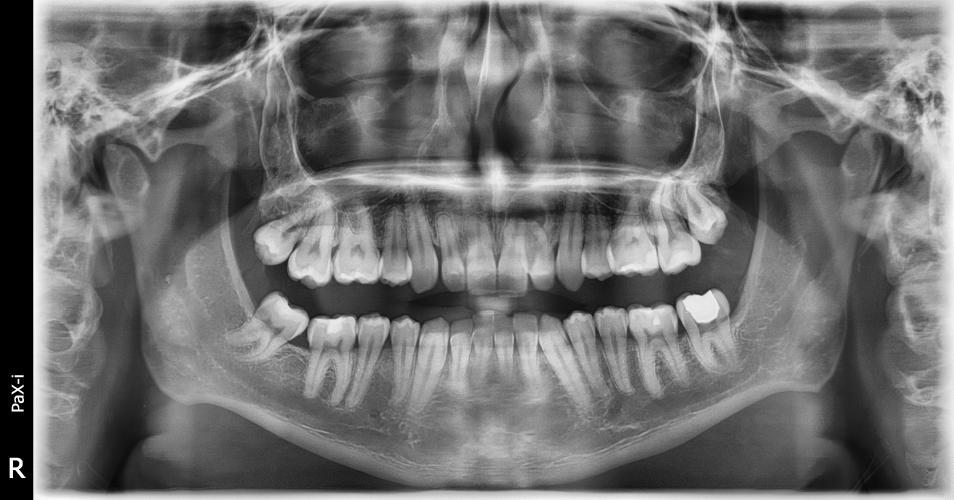

Question: S1 AM 1.7 Using the case history and the print of radiograph NB1_b, answer the following question on the answer score sheet. (Select ONE or MORE correct answers.) Which of the following is the most likely anatomical structure/diagnosis for the radiographic entity/entities?